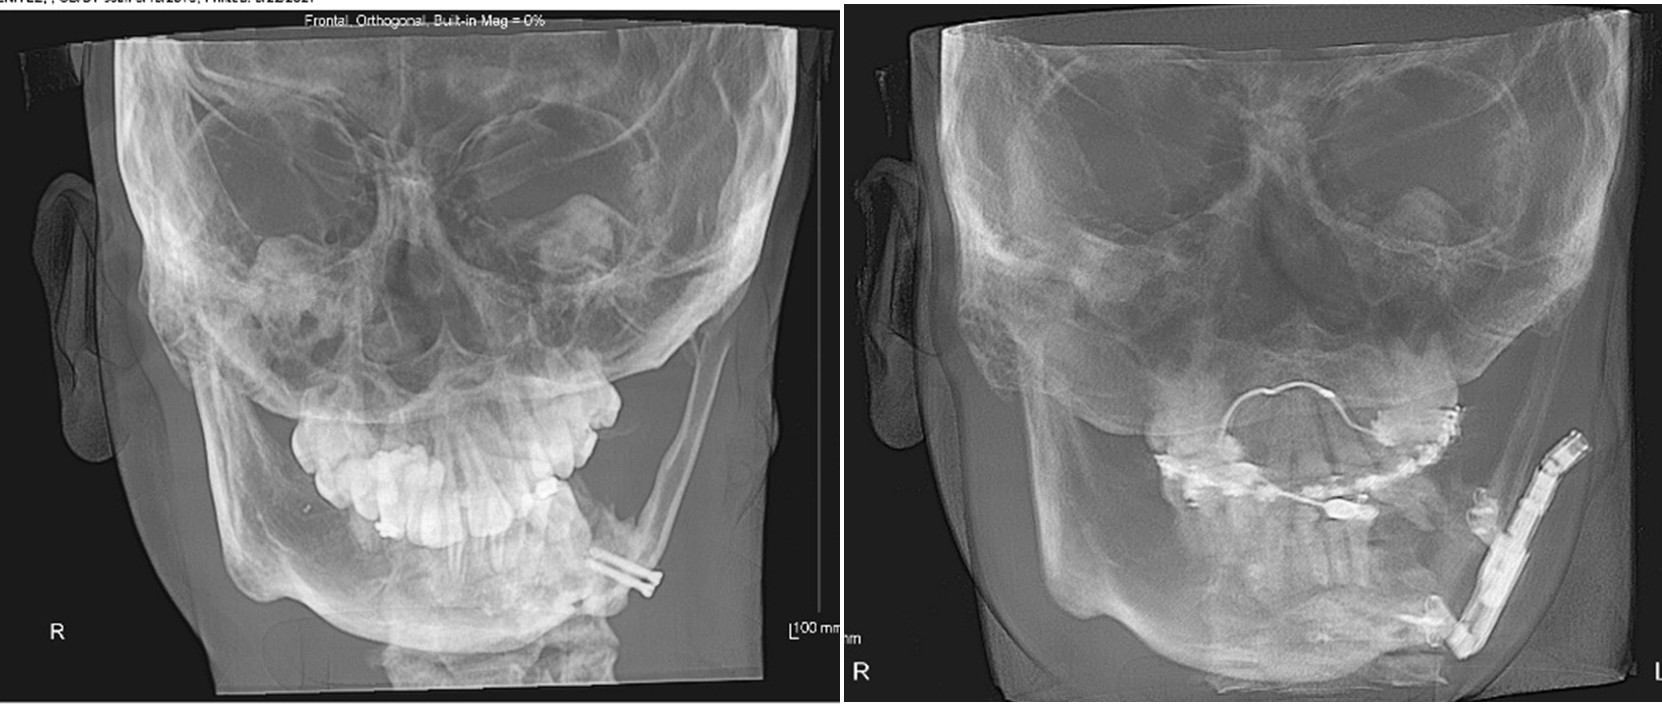

Craniofacial Orthodontics represents one of the most advanced and specialized fields within orthodontics. This highly focused area involves the treatment of patients with congenital or acquired craniofacial conditions such as cleft lip and palate, craniosynostosis, Hemifacial Microsomia, and other complex facial anomalies. Craniofacial orthodontists work closely with Multidisciplinary Teams—including plastic surgeons, oral surgeons, pediatricians, and speech therapists—to coordinate care that not only improves function and appearance but transforms lives. The complexity of these cases demands exceptional clinical skill, in-depth anatomical knowledge, and a high level of precision.

These specialists typically complete a Fellowship at a recognized craniofacial center, dedicating years to mastering advanced techniques and treatment planning for patients with intricate skeletal and dental irregularities.